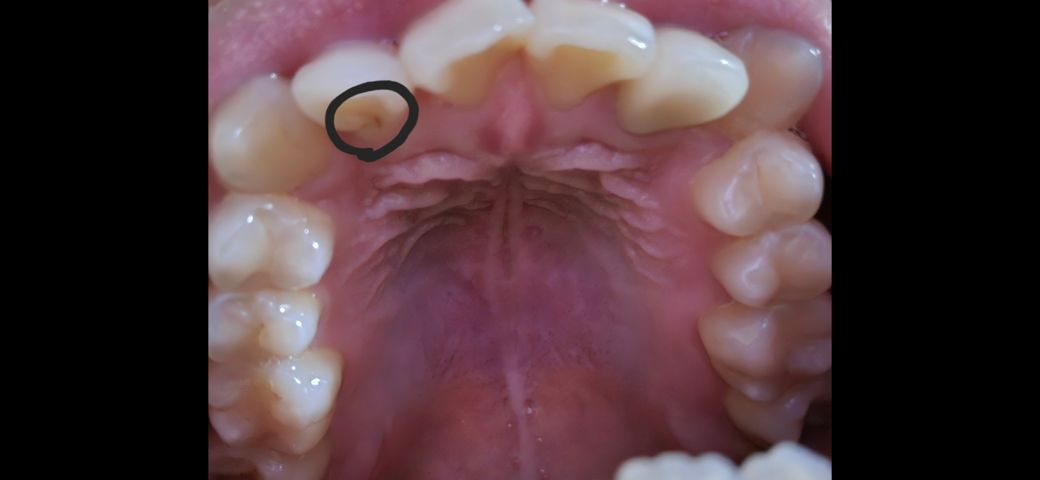

윗 앞니에 검은 선같은게 있는데 충치인가요?

사진처럼 윗 앞니에 검은 선이 있습니다 딱히 시리다거나 그렇진 않은데 혹시 충치인가요? 위의 좌우대칭되는 치아도 신경치료 후 크라운을 씌운상태라 걱정되네요 엑스레이 사진은 9월16일 사진입니다

• 1번 째 사진